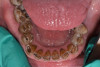

At a clinic treating patients in an underserved population, a 54-year-old female patient presented requesting extraction of all of her teeth and fabrication of dentures for her long-term restorations. The patient had a history of breast cancer, which had been treated with chemotherapy. She believed that full dentures would be an appropriate treatment option for her, owing to the poor state of her oral health and dentition and because she had limited financial resources and did not think that she could afford restoration of her teeth. The patient reported that she had experienced depression and alcohol abuse because of her cancer diagnosis, and that she had neglected her dental care during the course of her cancer treatment, resulting in generalized moderate-to-severe caries with moderate wear due to bruxism (Figure 1 through Figure 5). She also presented with significant staining of her remaining dentition due to the alcohol abuse.

Fig. 1